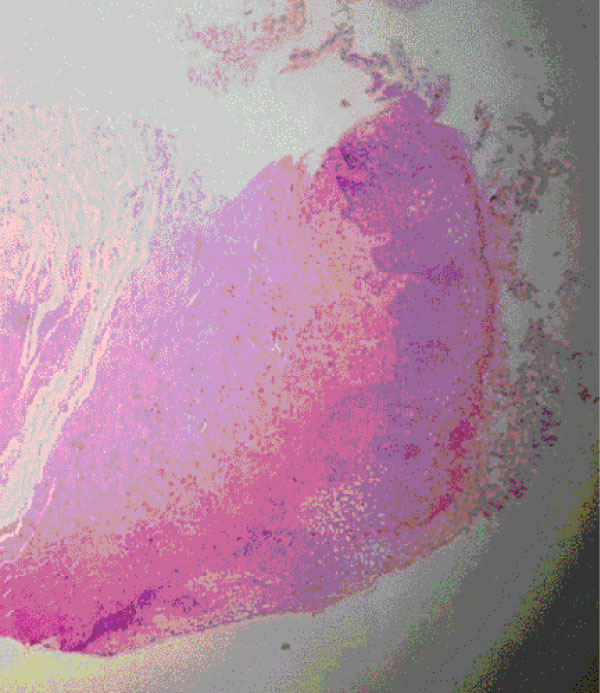

After four laser treatments (T4), study protocol complete, new biopsies were taken and the new vulvo-vaginal samples show almost a restauration to "normal" epithelium or, more correctly, to a pre-menopausal histological condition. As show in Figure 2 the coating of the epithelium is evident, the thickening of the derma surface con be observed together with a phenomenon as the glycogenic acanthosis causing the "glycogenization", a benefic process inducted by laser treatment. In addition, in the chorion we assisted to a gain in number and highness of papillae hand in hand with reduction of fibrosis. At last an increasing in fibroblastic activity was demonstrated generating a restauration in collagenic structure and causing angioblastic remodulation as can be seen with the appearance of what is called "angioblastic granulation tissue-like" Figure 2.

Figure 2: Vaginal sample at T4: Vaginal Histological modification induced by treatment. To be notice the thickening of the derma surface, the phenomenon of glycogenic acanthosis, the increased number and highness of papillae in chorion and the reduction in the inflammatory tissue infiltrate. View Figure 2